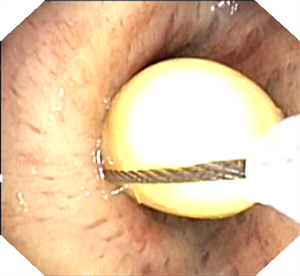

一位外地老年男性患者,因 “肺炎” 一直咳嗽、气喘不愈,活动量差。在当地医院多次住院治疗,症状仍无明显改善。后因 “液气胸” 急诊入我院,呼吸科医生仔细阅片后发现,患者右中间段支气管内有一类圆形 “新生物” 阻塞管腔。收住院后,呼吸内镜团队为患者进行全麻支气管检查,清晰见到右中间段支气管内一黄豆异物阻塞。由于异物 “圆滑”,直接取出困难,医生巧妙地用圈套器 “捆扎” 住黄豆,顺利完整拉出,患者快速康复出院。